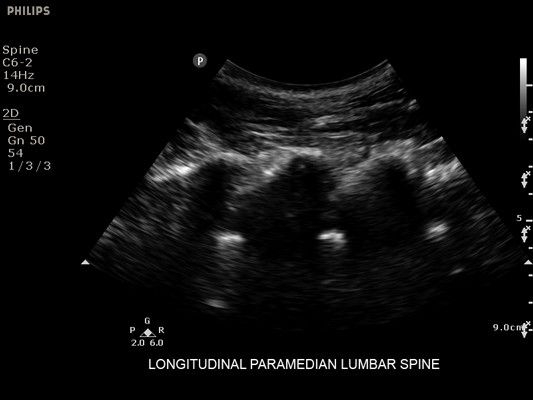

• Метки центральной линии на датчиках L12-4 и C6-2 для упрощения внеплоскостной навигации

• Конвексный УЗИ датчик Philips С6-2